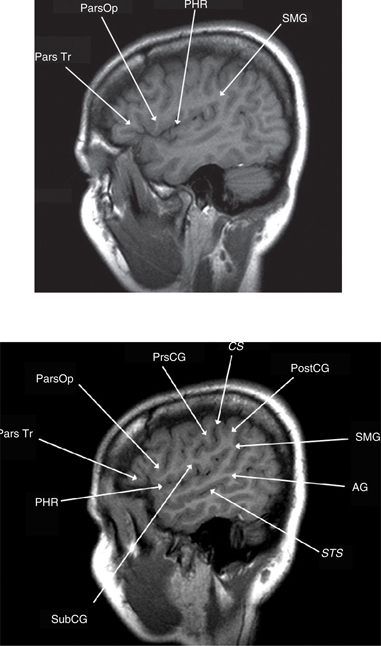

Eloquent cortex generally implies speech, sensorimotor, and visual areas. Broca’s area lies in the pars opercularis and triangularis of the IFG Brodman’s area 44 (Figure 3). It controls the complex orofacial movements required to articulate speech and lies just anterior to motor cortex for lip, tongue, face, and larynx movements. Additional essential language sites in the dominant hemisphere can extend into the MFG, STG, middle temporal gyrus (MTG), or the insula. Expressive aphasia results from injury to Broca’s area, while receptive aphasia results from injury to Wernicke’s area (Figure 3). Injury to the arcuate facsiculus or white matter tracts connecting these speech areas results in conduction aphasias with impaired repetition. Injury to association cortex around the speech areas results in transcortical aphasias in which the primary function is impaired but repetition is preserved. The fusiform gyrus may also participate in speech, “basal temporal language area,” although deficits from surgical resections in this area typically recover. Auditory functions are bilaterally represented and resections involving the transverse temporal gyri in one hemisphere are well tolerated. Optic radiations, representing the inferior half of the contralateral retina, loop forward over the temporal horn before arching back toward the striate cortex in the banks of the calcarine fissure. Temporal resections that encroach upon these fibers cause a contralateral upper outer quadrantonopsia, a “pie-in-the-sky” defect, which is also well tolerated (3, 1821).

Fig 3

Figure 3 Lateral sagittal T1-weighted MRI scans. Pars triangularis (Pars Tr), pars opercularis (Pars Op), posterior horizontal ramus of the sylvian fissure (PHR), and supramarginal gyrus (SMG). Subcentral gyrus (SCG), precentral gyrus (PCG), central sulcus (CS), postcentral gyrus (PoCG), supramarginal gyrus (SMG), angular gyrus (AG), and superior temporal sulcus (STS).